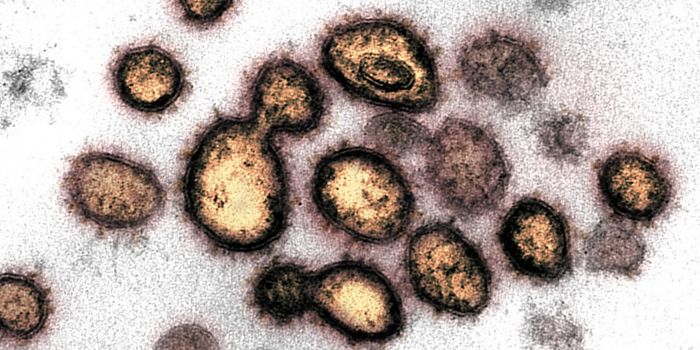

MAR 14, 2022ImmunologyThough it may happen at different rates for different microbes, mutations happen, and SARS-CoV-2, the virus that causes ...